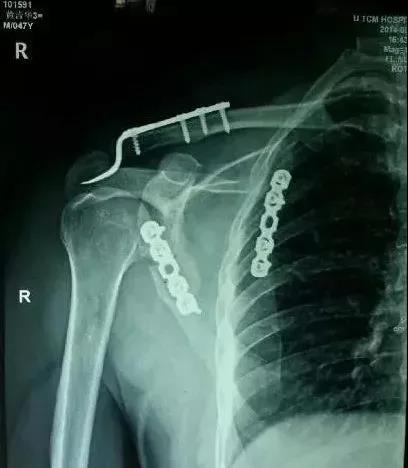

2)肩胛骨骨折

在2周之后手术,困难程度翻番。